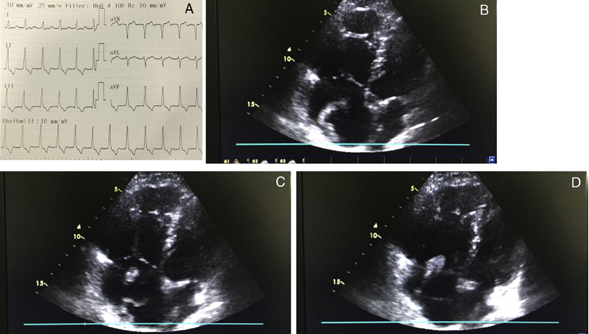

Hombre de 36 años, sin comorbilidades previas, quien dos semanas atrás presentó esguince de tobillo derecho al practicar deporte; acude al departamento de emergencias con historia de dolor torácico súbito, tipo punzada, de gran intensidad, irradiado al maxilar inferior y duración mayor a 30 minutos, el cual se acompaña de disnea en reposo, diaforesis y lipotimia. Se registró frecuencia cardiaca de 132 latidos por minuto, taquipnea y saturación de oxígeno de 90% con máscara de Venturi al 50%. El examen físico no mostró alteraciones en los ruidos respiratorios ni tampoco en la auscultación cardiaca. Se realizó electrocardiograma que mostró (fig. 1 panel A) taquicardia sinusal con signo de McGinn-White presente (S1Q3T3 - ondas S en DI, onda Q en DIII y onda T negativa en DIII). Se tomó troponina I ultrasensible que fue positiva. El ecocardiograma transtorácico mostró aurícula derecha dilatada con presencia de trombo móvil en su interior, que se extendía desde la vena cava interior, pasando el plano de la válvula tricúspide (fig. 1 panel B, C y D), ampliamente móvil; dilatación severa del ventrículo derecho, disfuncionalidad, TAPSE de 13 mm e incremento de la interdependencia ventricular. Recibió trombólisis intravenosa con activador del plasminógeno tisular en unidad de cuidados intensivos. Se realizó seguimiento ecográfico diario; no requirió ventilación mecánica y fue dado de alta de forma satisfactoria 15 días después del cuadro.